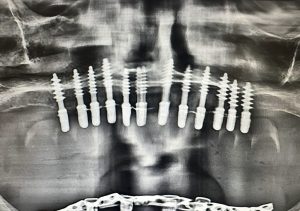

Caz concret inainte si dupa:

Implantul dentar rapid (sau immediate loading) înseamnă că implanturile dentare sunt inserate și o lucrare provizorie fixă este montată în aceeași zi sau în maxim 72 de ore.

Multe cazuri se rezolvă fără grefe de os suplimentare, datorită tehnicilor avansate (cum ar fi poziționarea strategică a implanturilor).

Astfel, durata tratamentului scade dramatic, iar intervențiile chirurgicale suplimentare sunt evitate.